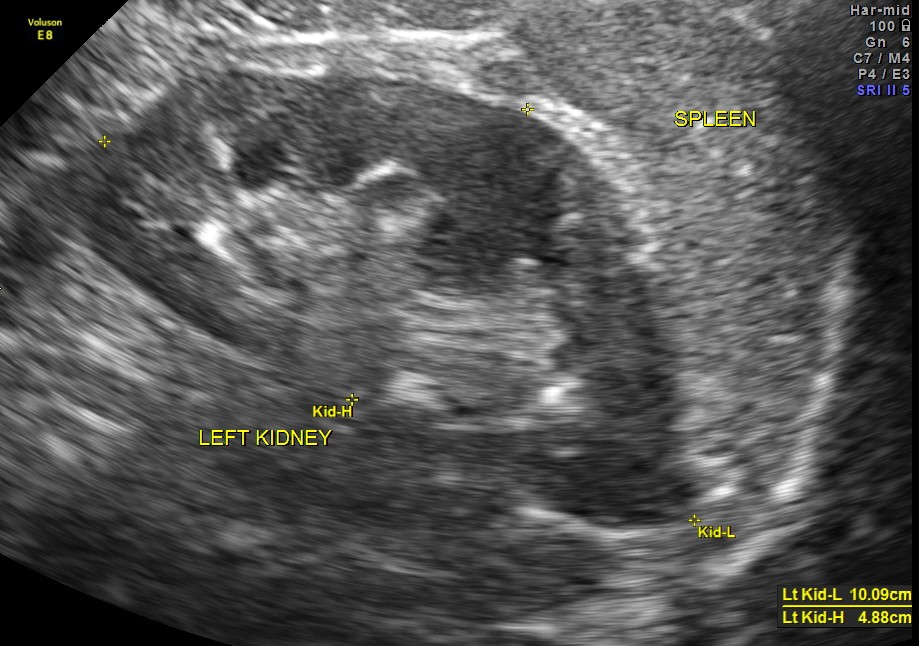

An ultrasound abdomen was done as part of evaluation of anemia.